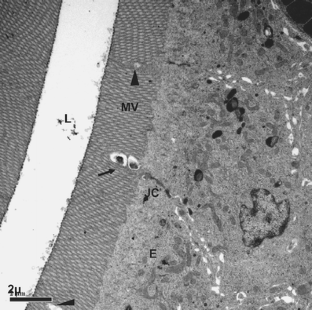

Furunculosis and vibriosis are diseases that cause severe economic losses in the fish-farming industry. The foregut of the Atlantic salmon (Salmo salar L.) was exposed in vitro to two fish pathogens, Aeromonas salmonicida (causative agent of furunculosis) and Vibrio anguillarum (causative agent of vibriosis), and to one probiotic strain, Carnobacterium divergens, at 6 × 104 or 6 × 106 viable bacteria per milliliter. Histological changes following bacterial exposure were assessed by light and electron microscopy. Control samples (foregut exposed to Ringer’s solution only) and samples exposed only to C. divergens had a similar appearance to intact intestinal mucosal epithelium, with no signs of damage. However, exposure of the foregut to the pathogenic bacteria resulted in damaged epithelial cells, cell debris in the lumen, and disorganization of the microvilli. Co-incubation of the foregut with a pathogen and C. divergens did not reverse the damaging effects caused by the pathogen, although these were alleviated when probiotic bacteria were used. Based on these results, we suggest that the probiotic bacterium, C. divergens, is able to prevent, to some extent, pathogen-induced damage in the Atlantic salmon foregut.

Fig. 1

Fig. 2

Fig. 3

Fig. 4

Fig. 5

Fig. 6